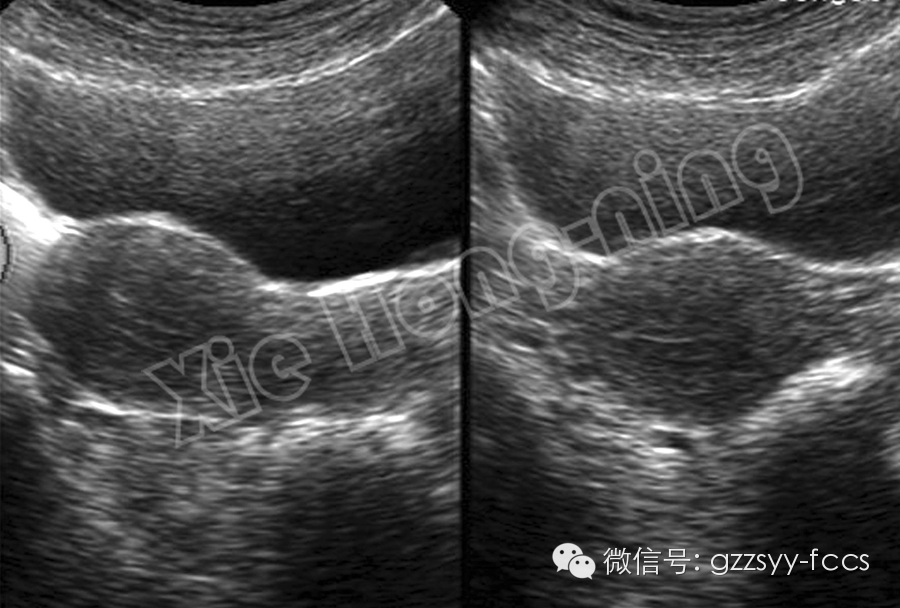

經腹二維超聲顯示子宮結構

經陰道超聲顯示子宮結構更清楚